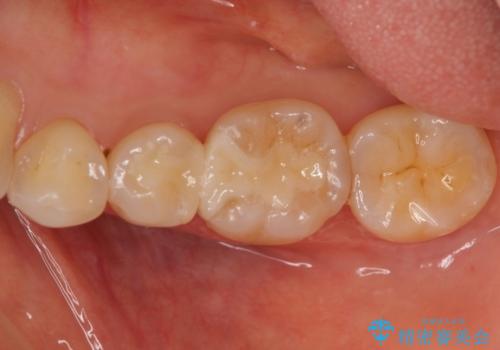

目立つ銀歯を全て白く セラミックで虫歯治療

- 銀の詰め物が気になるとのことで来院。

2本隣り合っているつめものを、同時にやりかえをしました。

- 14万円(左下5・左下6 emaxプレスインレー 7万円 x 2)費用は治療当時の料金となります

向かい合う銀歯を同時にやり変えることで、コンタクト(歯と歯の間の形)を理想的に仕上げることができ、ものも挟まりにくいように仕上げることができます。